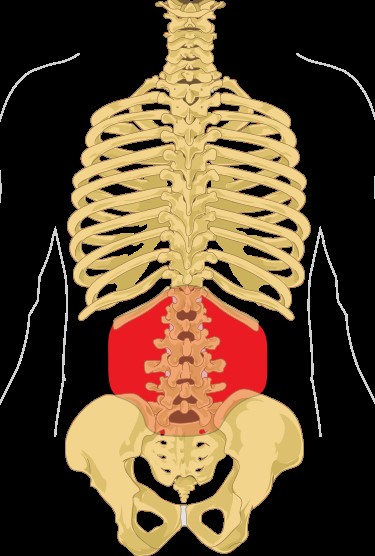

DXA可以檢查身體任何部位的骨密度,但最常用來檢查髖骨以及腰椎的骨密度。

腰椎 |